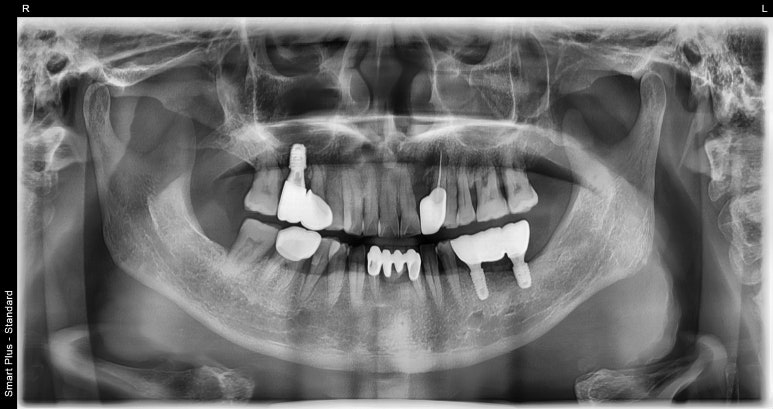

임플란트브릿지 치료후

2023-06-22

이처럼 여러 개의 치아가 결손되어 임플란트를 식립해야 할 때 치아 개수대로 임플란트를 식립할 수도 있지만,

지금 환자분 케이스처럼 중간에는 브릿지처럼 파닉으로 연결하는 케이스도 있습니다.

임플란트브릿지는 결손된 치아 개수대로 임플란트를 식립하지 않아도 되기 때문에

환자분의 체력적, 경제적인 부담을 덜 수 있어 가능한 경우 널리 활용되는 치료 방법입니다.

다행히 환자분의 경우 3월 말 임플란트 수술 후 약 2개월 후에 진행된 수치 측정

(임플란트 인공치근이 잇몸뼈와 잘 유착되었는지를 확인하기 위한 측정 단계) 결과가 양호해

2주일 후 치아역할을 하는 브릿지까지 완전히 접착해 드렸습니다.